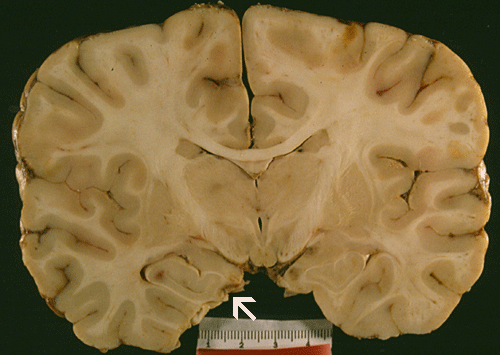

Gross pathology: The brain weighs 1,650 grams (normal is 1,320 grams and was grossly edematous. The leptomeningeal surface appears slightly granular and this feature is best appreciated on side lighting (Arrow in Panel A). On coronal sections, the lateral ventricles are totally collapsed and the sulci are flattened out by the edema. There are some poorly defined brownish, round patches in the cortex and thalamus. The uncal notch on the left side (Panel  B) appears deep, brownish and friable whie the uncal notch in the right side appear deep. There are focal necrosis in the orbital frontal lobe, bilateral olfactory bulbs, and bilateral temporal lobes.

The brain is extremely edematous and therefore heavy as illustrated in our case. The extreme edema will produce uncal and tonsillar herniation which is usual cause of death. There is a thin layer of purulent exudates on the leptomeninges. On cross sections, small hemorrhagic foci can be observed.